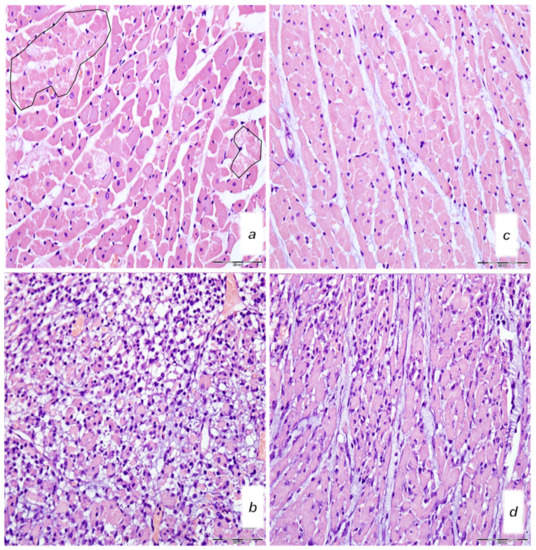

2.8.4. Renal, Liver and Heart Histology

2.8.5. Gastrointestinal Histology